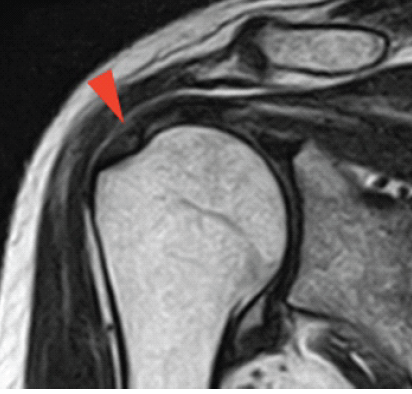

Painful Biceps Vincula: An Unrecognized Cause of Anterior Shoulder Pain

Alex E. White , Matthew R. Bryan , Christopher Fenelon , Samuel A. Taylor , Stephen J. O'Brien ………………………………p.463-467